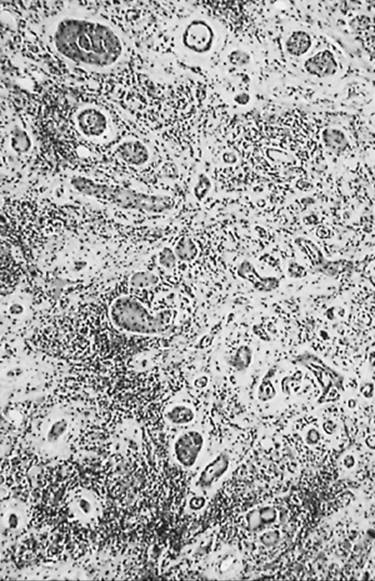

Microscopic examination shows that most clinically evident papillary cancers contain papillae (Fig. 21.12); however, papillae may constitute only a tiny part of the neoplasm. Papillary cancer may be solid, may be composed of follicles (Fig. 21.13), which is classified as follicular variant, or may be almost entirely papillary (125,148,149,150,151,164,165). Trabecular (150,164), cribriform (150), and diffuse (125,151,165,166,167,168,169,170,171), patterns occur (Fig. 21.14).

FIGURE 21.12. Papillary carcinoma with papillae of various sizes.

FIGURE 21.13. Papillary carcinoma with a follicular pattern. Nuclei vary in size and shape, and some have clear centers.

FIGURE 21.14. Papillary carcinoma with extensive fibrosis, chronic inflammation, and squamous metaplasia.